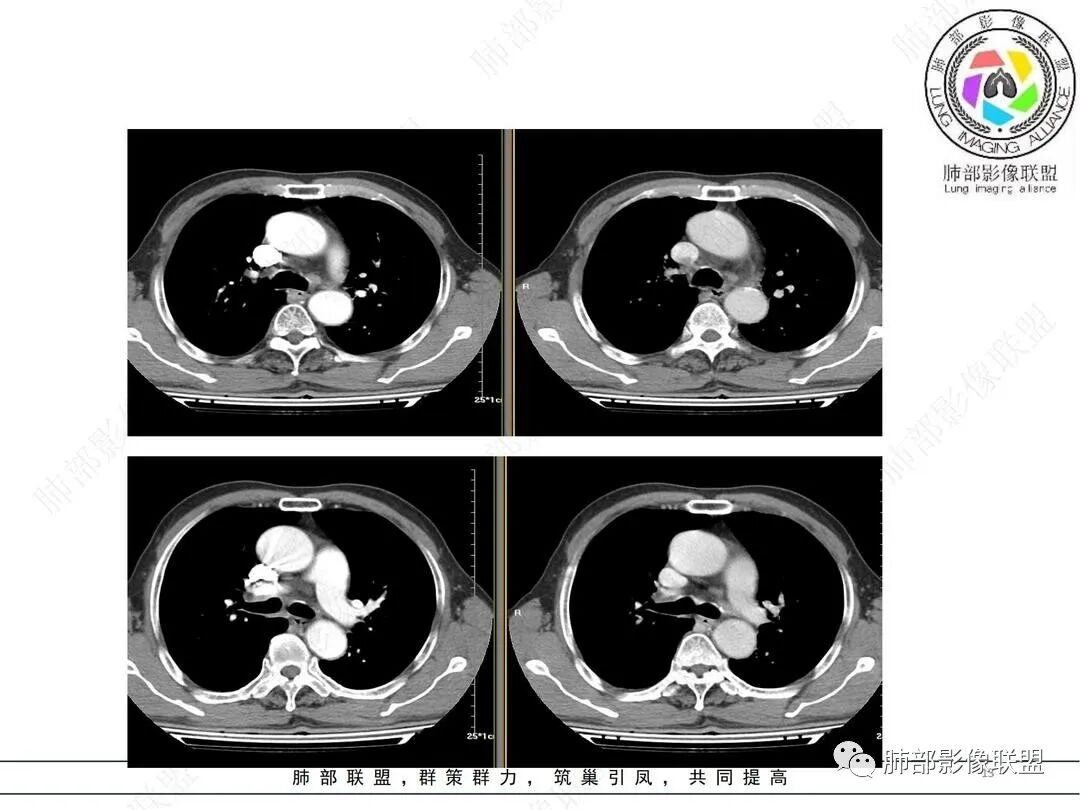

水晶石头:患者中老年男性,咳嗽、咳痰2周。查血常规血象升高。胸部CT:右肺下叶肺门区高密度结块影,部分稍膨隆,部分平直,边界清楚,边缘光滑,增强强化明显。综合考虑良性炎性病变。

支持鳞癌证据:1.支气管壁增厚 ;2.实变内含小粘液栓;3.实变部分有些膨隆

支持结核证据:1.病史较短,结核抗体阳性,炎性指标高;2.肺野内有小树芽征;3.流入强化,实变内似见环形强化;4.多支气管累及(病变太广泛不利于鳞癌诊断?待验证);5.实变部分略呈三角形?

放射线:右肺下叶内基底段软组织肿块,边界清楚,相对比较圆钝,沿支气管长轴生长,内未见明显的坏死,远端未见阻塞性改变,老年男性,考虑小细胞肺癌>鳞癌。

张延军:右肺门区软组织肿块,内基底段支气管壁增厚,管腔局部狭窄,增强后见环形强化影,中叶肺组织内见树芽及斑片状高密度影,界不清,肿块边缘平直,且累及到7区,支气管似受压改变,考虑炎性肉芽肿可能性,恶性待排。

第1个问题:是否是近端支气管堵塞?腔内肿瘤导致远端阻塞性改变?还是外围病灶围绕支气管,引起堵塞?

第2个问题:病灶是否就是内基底段?

第3个问题:支气管堵塞?还是堵塞后还有通畅支气管?

(1)病灶形态和分布:双肺散在点片影,可见树芽征。右肺下叶内基底段实性密度团块状影,底部坐落膈面、浅分叶,略呈圆锥形沿血管支气管束探及肺门,可疑“支气管爬行征”。奇食窝区分出子灶。病灶轻中度强化不均,斑片状低密度无强化区,疑坏死,未见钙化。右肺门及淋巴结肿大。

(2)支气管和血管:右肺支气管分支管壁弥漫性增厚,中间段支气管散在结节样凸起,右肺下叶内基底段支气管闭塞,但远端可疑复出。余病灶围绕支气管腔内远端无明显阻塞性不张。内部血管走形自然,提示包绕为主。